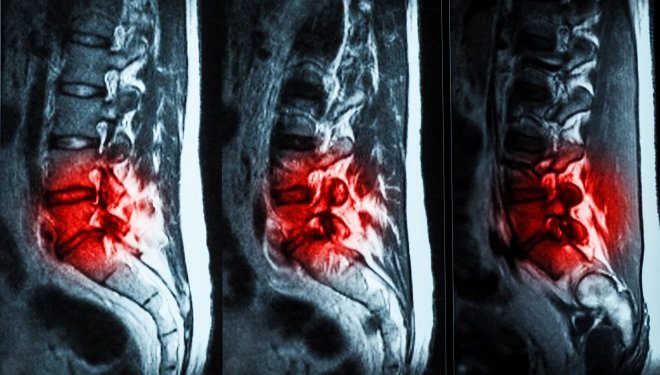

Хроническими болями в пояснице по причине изношенности межпозвоночных дисков страдают миллионы людей. Основная функция дисков — амортизация позвонков. Однако со временем диски изнашиваются, находящаяся внутри них жидкость вытекает, из-за чего их амортизационная функция снижается, что вызывает боли в позвоночнике и даже приводит к инвалидности.

Специалисты компании ReGelTec разработали гидрогель Hydrafil, который при введении в позвоночник заполняет трещины и травмы поврежденных дисков, частично восстанавливая утраченную амортизацию и снимая боль. В настоящее время препарат проходит испытания с участием 20 добровольцев, страдающих от хронических болей в пояснице, в возрасте от 22 до 69 лет.